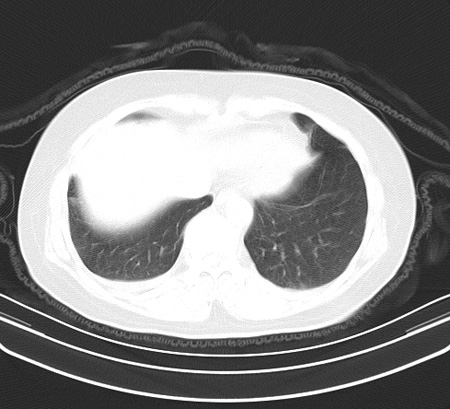

以下是引用余辉在2009-2-19 20:10:00的发言:[br]多考虑急性感染性病变,右中叶尚可见多枚小斑片状影,多为化脓性肺炎,双侧胸腔积液

以下是引用随光逐影在2009-2-19 20:33:00的发言:[br]1)考虑右肺炎症;建议抗炎治疗后复查。2)双侧胸腔积液(以右侧为甚)。

以下是引用花凤凰在2009-2-19 20:46:00的发言:[br]病人有发热,胸痛急性起病,主要病变位于右肺中叶外侧段,呈楔行改变,位于外带胸膜下,考虑为肺梗塞可能!!!!!!!!!!!!!!!!!!!!!!!!!!!!!!!!!!!